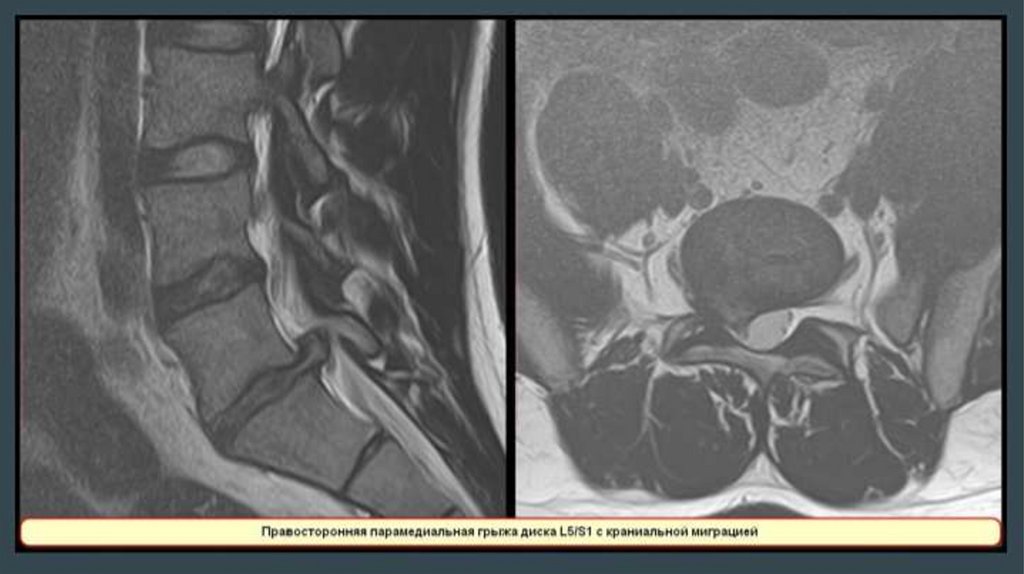

Анатомия позвоночника

Грыжа

межпозвонково

го диска

16.

17.